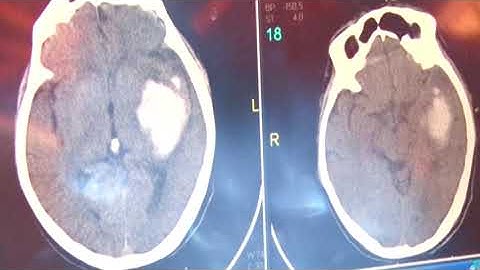

Ứng dụng Trí tuệ Nhân tạo trong cấp cứu đột quỵ| VTC14